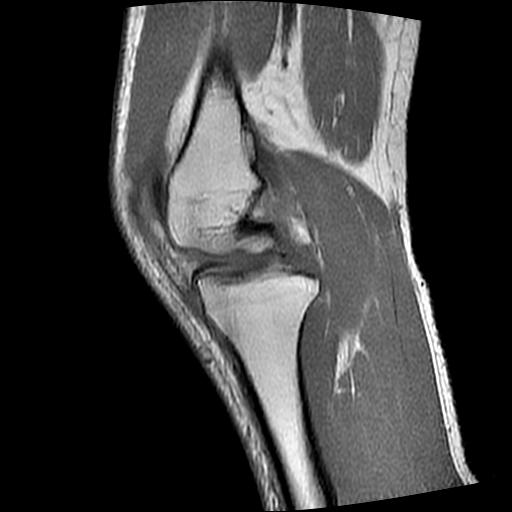

标题: MRI1265:男性40岁,右膝关节 [打印本页]

标题: MRI1265:男性40岁,右膝关节

40岁男性,右膝关节外伤,x光平片示,髁间隆突撕脱骨折。

1、前交叉韧带撕裂;

2、外侧半月板后角撕裂;

3、关节腔积液。

前交叉韧带撕裂,关节腔积液.

半月板1-2级损伤   前交叉韧带撕裂伤   关节腔少量积液  诸骨未见新鲜外伤性改变

髁间隆突撕脱骨折;内侧副韧带损伤。

内侧副韧带撕裂及关节腔积液是肯定的,但是前交叉撕裂确定吗?会不会有容积效应的因素,因为前一张前交叉显示清楚,连续性良好,且较光滑。请问楼主有关节镜支持吗?我们医院也经常有这样的患者,但苦于没有关节镜,而无法对照、证实(除非完全断裂),出现了不同的诊断结果只能毫无意义的争论。

1、前交叉韧、内侧副韧带撕裂;

3、关节腔积液。4、髁间脊撕脱骨折。

除了关节积液外并无韧带撕裂,acl胫侧附着点有2束,正常情况下脂肪信号。此病例应加做压脂像以便观察是否有骨损伤。